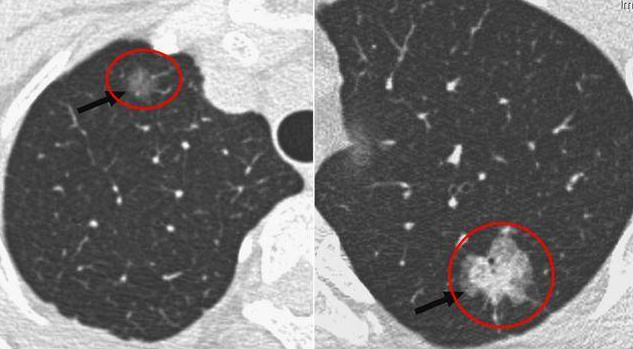

通常有三种类型的肺结节,即实性结节、磨玻璃结节和混合结节。磨玻璃结节模糊不清,无法清晰观察。

如果不能消失,则应根据其变化判断良恶性,如生长较快或由纯磨玻璃结节变为混合磨玻璃结节,中间出现实性阴影,则认为恶性可能性较大,应尽早手术进行基础治疗。